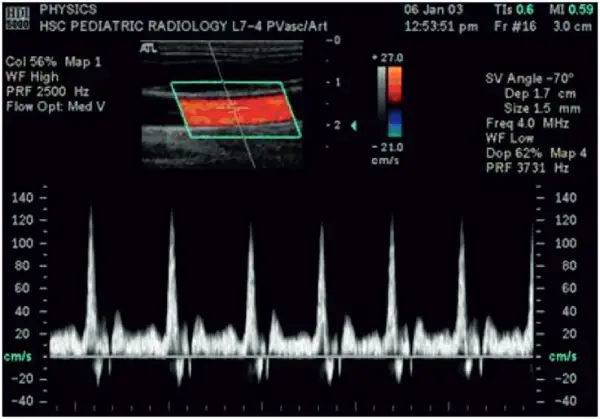

Doppler Sonography

Sonography can be enhanced with Doppler measurements, which employ the Doppler effect to assess whether structures (usually blood) are moving towards or away from the probe, and its relative velocity. By calculating the frequency shift of a particular sample volume, for example a jet of blood flow over a heart valve, its speed and direction can be determined and visualised. This is particularly useful in cardiovascular studies (sonography of the vasculature system and heart) and essential in many areas such as determining reverse blood flow in the liver vasculature in portal hypertension. The Doppler information is displayed graphically using spectral Doppler, or as an image using color Doppler (directional Doppler) or power Doppler (non directional Doppler). This Doppler shift falls in the audible range and is often presented audibly using stereo speakers: this produces a very distinctive, although synthetic, pulsing sound.

With the help of Color Doppler U/S blood flow in both can be diagnosed.